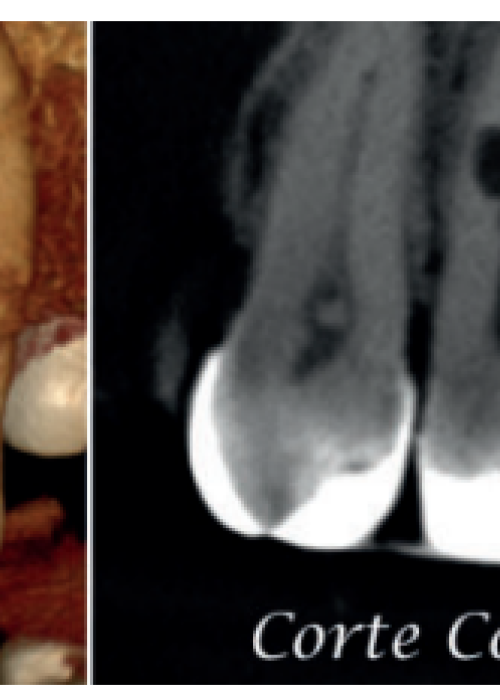

Actitud terapéutica frente a una reabsorción interna perforante